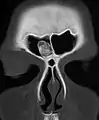

Osteoma represents the most common benign neoplasm of the nose and paranasal sinuses. The cause of osteomas is uncertain, but commonly accepted theories propose embryologic, traumatic, or infectious causes. Osteomas are also found in Gardner's syndrome. Larger craniofacial osteomas may cause facial pain, headache, and infection due to obstructed nasofrontal ducts. Often, craniofacial osteoma presents itself through ocular signs and symptoms (such as proptosis).[2]